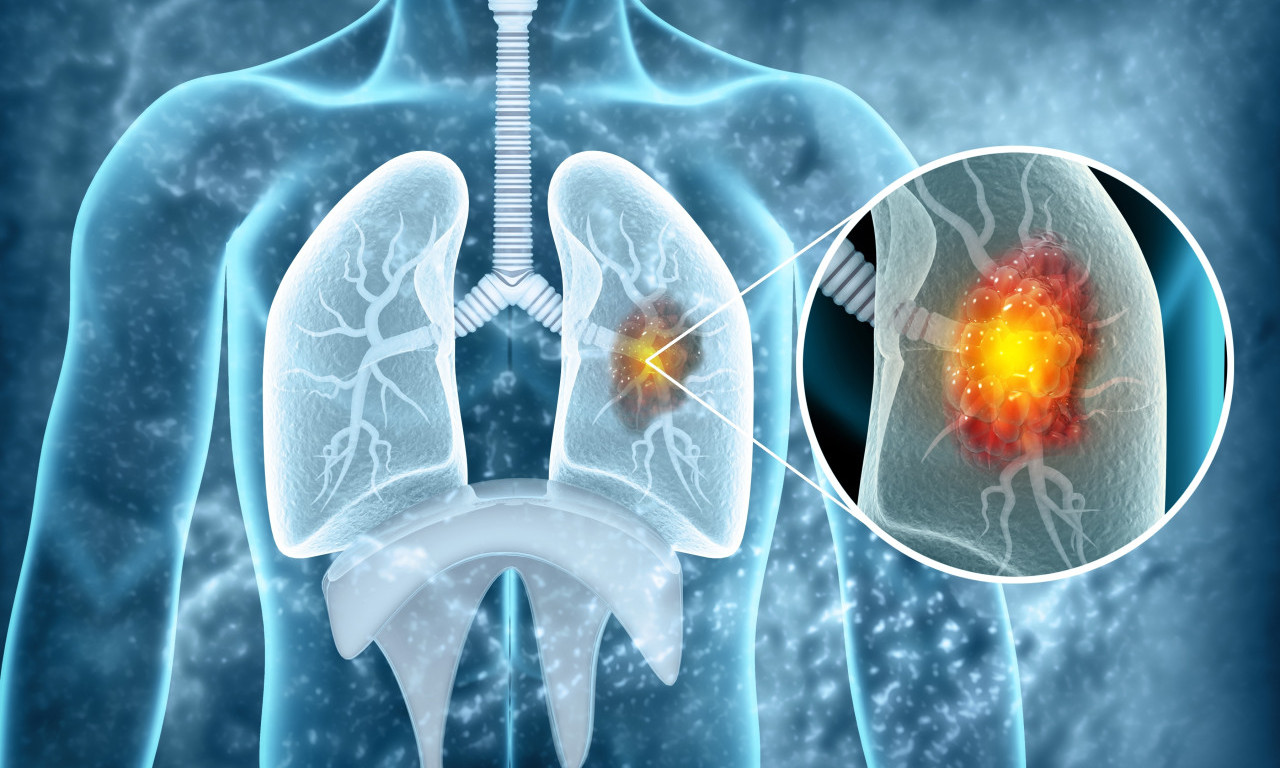

rak pluća

VEŠTAČKA INTELIGENCIJA OTKRIVA RAK PLUĆA MESEC DANA UNAPRED! Potrebno je uraditi osnovne medicinske analize

Na svaka dva sata u Srbiji jedna osoba premine od KARCINOMA PLUĆA! Od jeseni počinje "borba" u SRBIJI, a evo i kako

Svetski dan borbe protiv raka pluća obeležava se svake godine 1. avgusta.

Da li je NOVI LEK rešenje globalnog problema? Lekari objavili da najefikasnije zaustavlja RAK PLUĆA

Rak pluća je vodeći uzrok smrti od raka u svetu, a godišnje ima 1,8 miliona smrtnih slučajeva od kancera pluća

CRNA STATISTIKA: 70% obolelih RAK PLUĆA otkrije tek kad su ŠANSE ZA IZLEČENJE MINIMALNE, ovo je NAJVEĆI PROBLEM

Doktor je objasnio koje metode lečenja postoje u Srbiji i na koji način se određuje da li će pacijent biti podvrgnut inovativnom lečenju